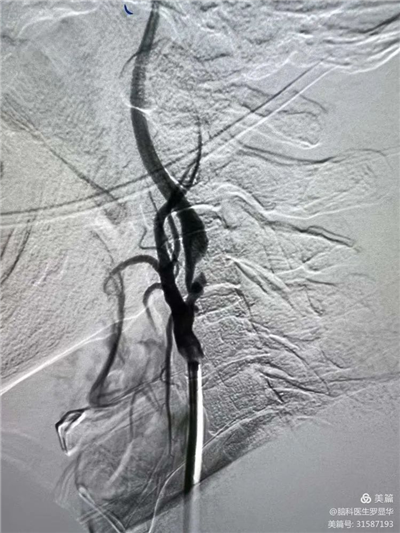

手術(shù)過程:球囊擴張后,protege支架到位

術(shù)后造影示狹窄解除